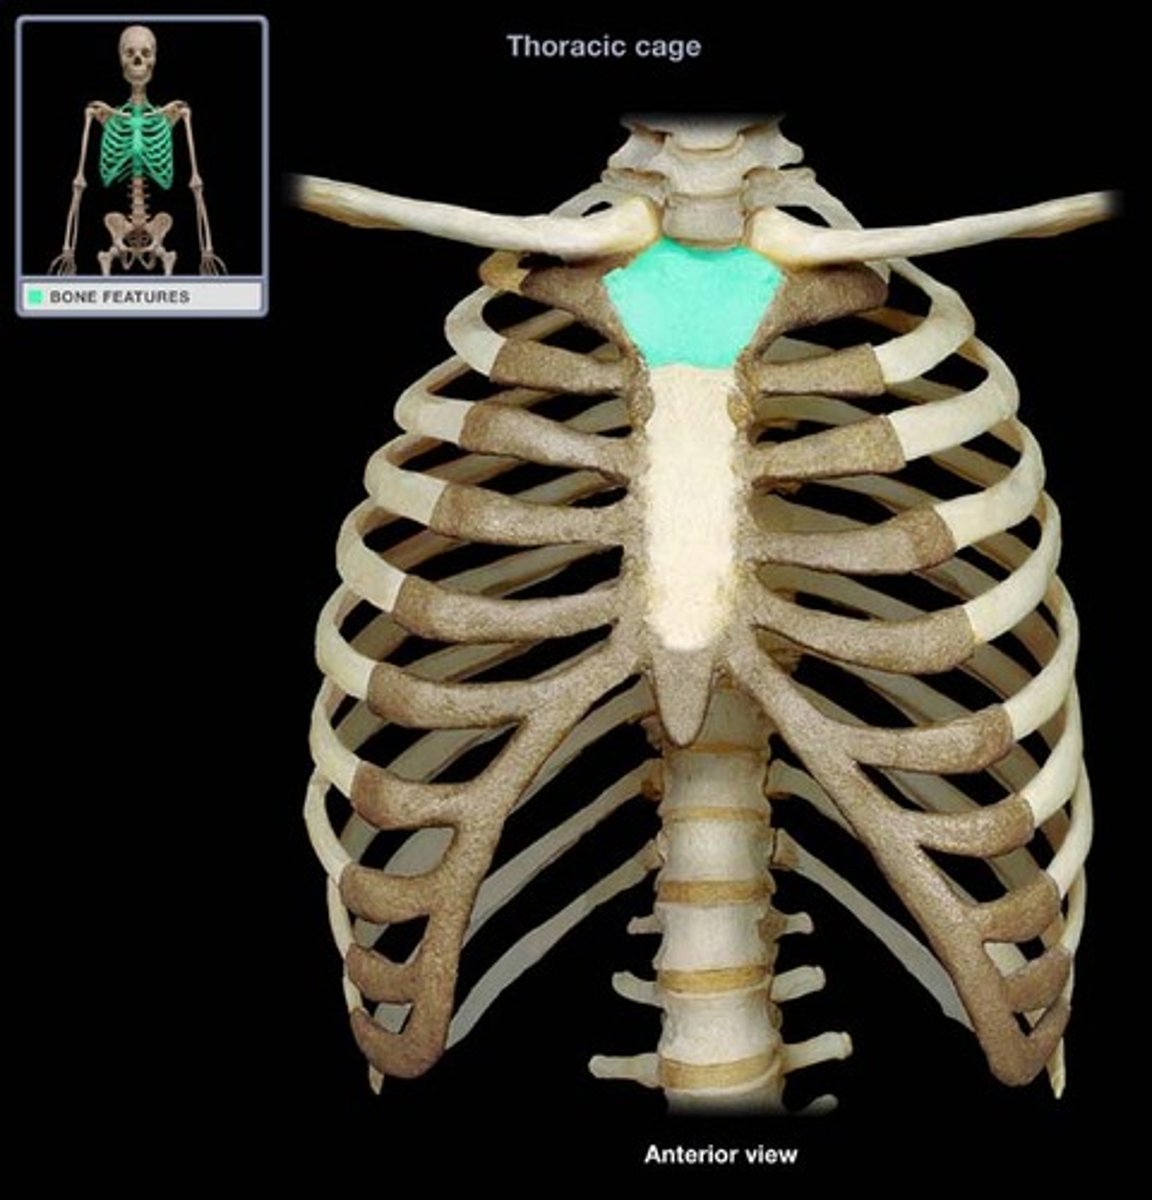

What makes up the thoracic cage?

sternum, ribs, and thoracic vertebrae

What is the function of the thoracic cage?

Protects heart, lungs, trachea, esophagus, and other thoracic organs, support upper limbs and provide muscle attachments

manubrium of sternum

Articulates with ribs 1, 2, & clavicles. Sternocleidomastoid muscles also attach here.

suprasternal (jugular) notch

superior surface of manubrium; u shaped notch

clavicular notch of sternum

Site where manubrium articulates with the clavicles

costal notches of sternum

indentations on sternum where costal cartilages from the ribs articulate

sternal angle

Ridge between manubrium and body at second rib

Xiphoid process of sternum

(T10)

Midline marker for superior level of liver, central tendon of diaphram

inferior border border of heart

cartilaginous in young people. Bone after 40.

thoracic cage

ribs, sternum, thoracic vertebrae, encloses organs and moves for ventilation